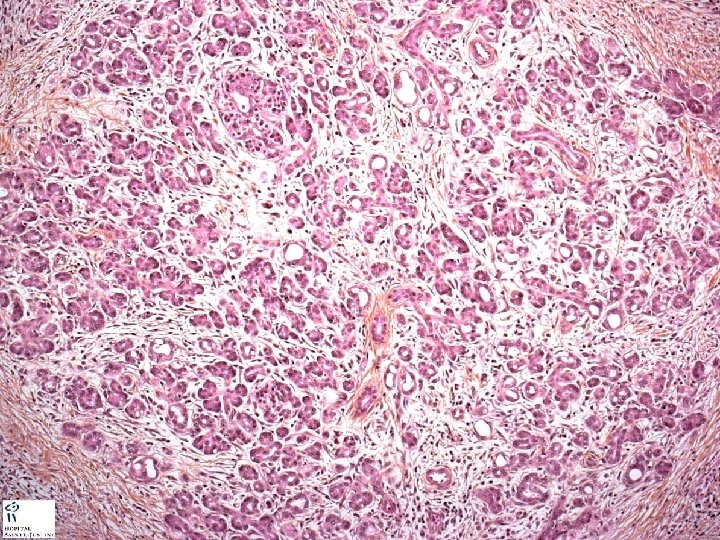

Hyperplastic pancreatic Islets of Langerhans. Chronic inflammation. Stromal fibrosis. Distorted pancreatic acinii.